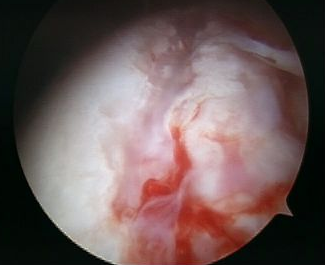

Arthroscopy

Anterior labral tears

Anterior capsule tears

Normal humeral insertion on right, HAGL on left with tearing of IGHL insertion onto humeral neck